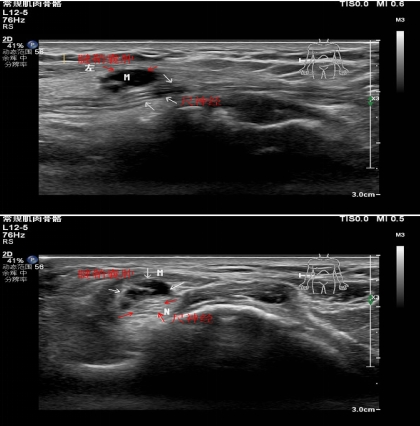

2.肘管綜合征